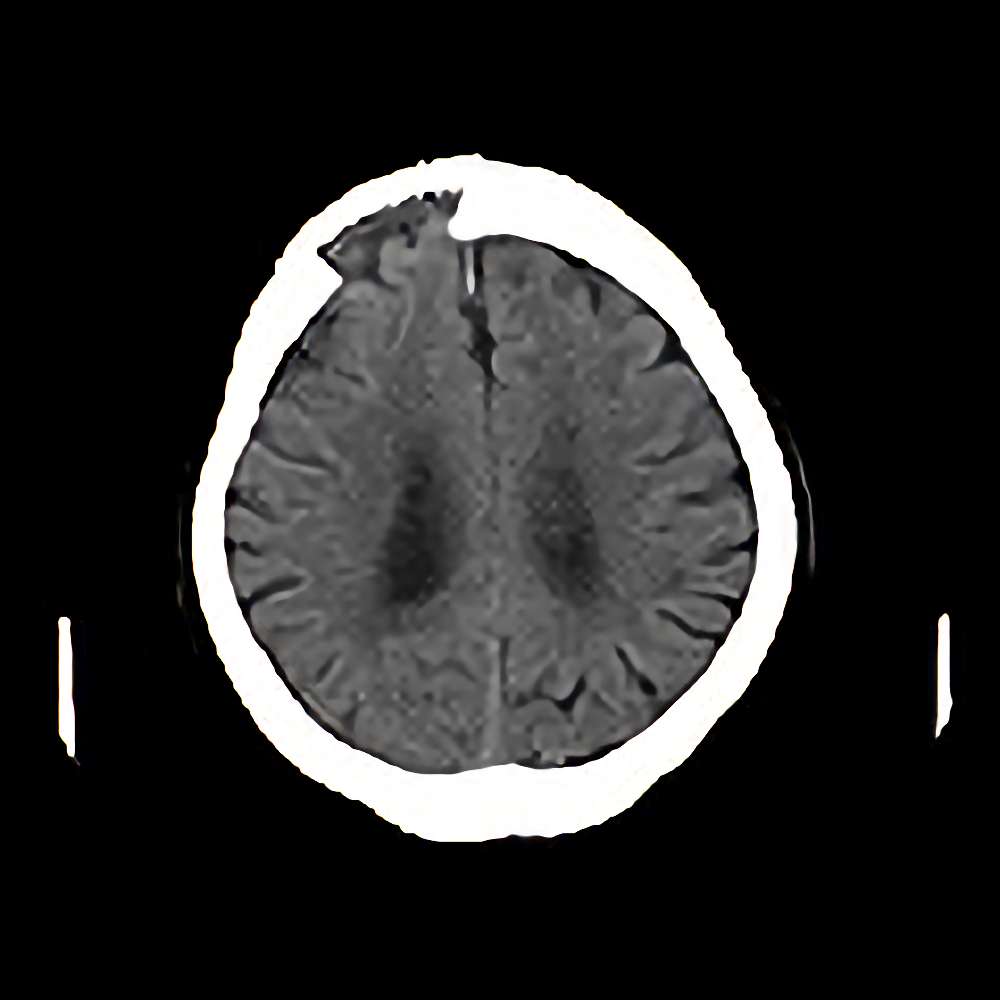

脳腫瘍

(頭蓋骨)

断層撮影

手術前1

No.’12_112 手術前1